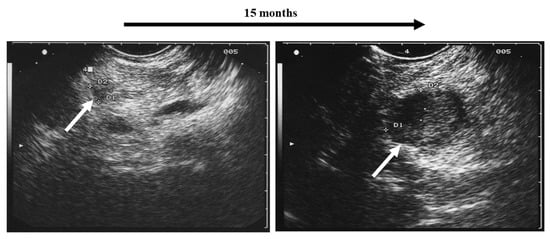

- Collienne, M.; Timmesfeld, N.; Bergmann, S.R.; Goebel, J.; Kann, P.H. Adrenal incidentaloma and subclinical Cushing’s syndrome: A longitudinal follow-up study by endoscopic ultrasound. Ultraschall Med. 2017, 38, 411–419. [Google Scholar] [CrossRef] [PubMed]

- Schaefer, S.; Shipotko, M.; Meyer, S.; Ivan, D.; Klose, K.J.; Waldmann, J.; Langer, P.; Kann, P.H. Natural course of small adrenal lesions in multiple endocrine neoplasia type 1: An endoscopic ultrasound imaging study. Eur. J. Endocrinol. 2008, 158, 699–704. [Google Scholar] [CrossRef]